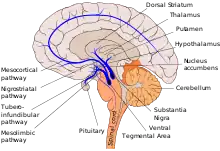

Five major pathways in the brain connect other brain areas to the basal ganglia. These are known as the motor, oculomotor, associative, limbic, and orbitofrontal circuits. Names indicate the main projection area of each circuit.[92] All are affected in PD, and their disruption causes movement-, attention- and learning-related symptoms of the disease.[92] Scientifically, the motor circuit has been examined the most intensively.[92]

Since 1980, a particular conceptual model of the motor circuit and its alteration with PD has been of influence although some limitations have been pointed out which have led to modifications.[92] In this model, the basal ganglia normally exert a constant inhibitory influence on a wide range of motor systems, preventing them from becoming active at inappropriate times. When a decision is made to perform a particular action, inhibition is reduced for the required motor system, thereby releasing it for activation. Dopamine acts to facilitate this release of inhibition, so high levels of dopamine function tend to promote motor activity, while low levels of dopamine function, such as occur in PD, demand greater exertions of effort for any given movement. The end result of dopamine depletion is to produce hypokinesia, an overall reduction in motor output.[92] Drugs that are used to treat PD, conversely, may produce excessive dopamine activity, allowing motor systems to be activated at inappropriate times and thereby producing dyskinesias.[92]